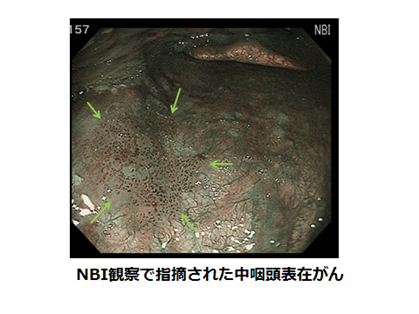

Case5 胃癌 下咽頭癌 食道癌の重複癌に対する治療戦略 ケース

Case5 胃癌 下咽頭癌 食道癌の重複癌に対する治療戦略 ケース

検査から抜けがちな頭頸部 意識的に検査し頭頸部がんを早期発見